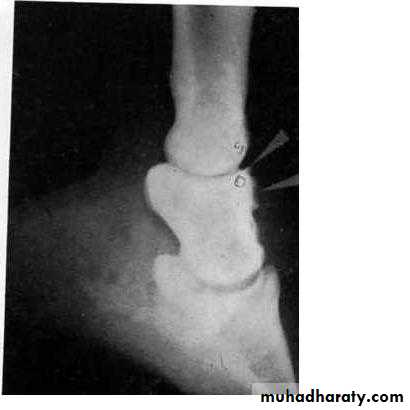

Lateral radiographs of the foot reveal the fracture or a separated extensor process.

Fracture of the extensor process of the distal phalanx (Arrow)